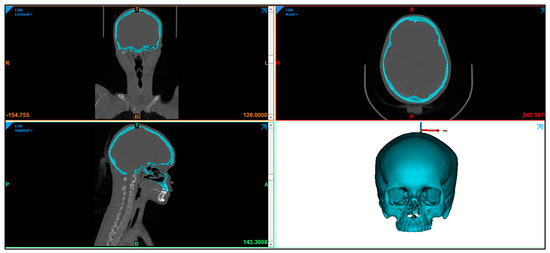

2.1. Image Acquisition and Processing